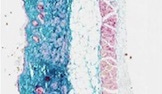

Image: Skin histology. Masson’s trichrome staining of a ground control mouse showing the different skin layers

A significant reduction of dermal thickness (−15%, P=0.05) was observed in S mice accompanied by an increased newly synthetized procollagen (+42%, P=0.03), likely reflecting an increased collagen turnover. Transcriptomic data suggested that the dermal atrophy might be related to an early degradation of defective newly formed procollagen molecules. Interestingly, numerous hair follicles in growing anagen phase were observed in the three S mice, validated by a high expression of specific hair follicles genes, while only one mouse in the G controls showed growing hairs. By microarray analysis of whole thickness skin, we observed a significant modulation of 434 genes in S versus G mice. A large proportion of the upregulated transcripts encoded proteins related to striated muscle homeostasis.